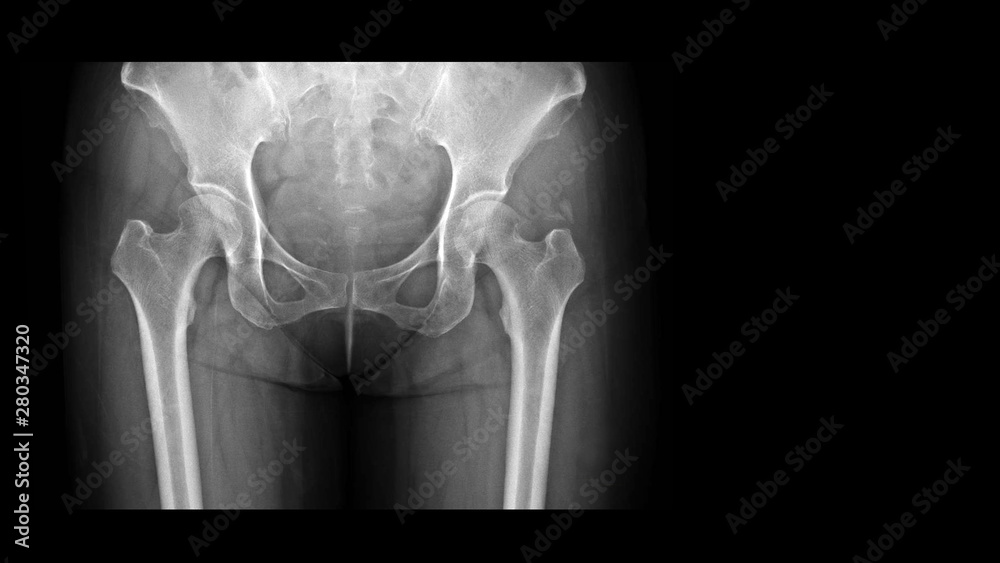

From stock.adobe.com

Film Xray hip radiograph showing calcium deposit on abductor tendon of Calcium Deposits On X Ray  The classification depends on the size of the calcium.   doctors classify nephrocalcinosis as molecular, microscopic, or macroscopic.   calcium pyrophosphate dihydrate deposition (cppd) disease, also known as pyrophosphate arthropathy or pseudogout, is defined.   medial artery calcification (mac) is a condition characterized by the presence of diffuse calcium deposits.   abdominal calcifications are common and have many causes. . Calcium Deposits On X Ray.